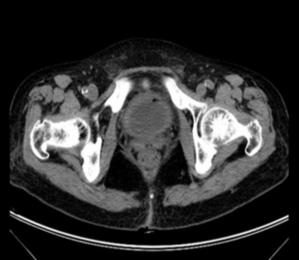

The laboratory findings of the 13 patients are shown in Table 2. All patients had an increased leukocyte count in the routine urine. The average leukocyte count of the patients was 2423.8±3441.2/μL (range 128-10933/μL). A majority (76.9%) of the patients had hematuria. The fasting blood glucose ranged from 8.4 to 19.4 mmol/L with an average of 12.1±3.1 mmol/L. The glycated hemoglobin (HbA1c) ranged from 6.6% to 11.3% with an average of 8.3±1.3%, reflecting poor glycemic control within the last two months. Two patients had azotemia, and two had proteinuria/hypoalbuminemia. All patients underwent abdominal CT, which revealed gas formation within the lumen or wall of the bladder (Figure 1).

Figure 1: Computed tomography reveals a circumferential intramural (arrow 1) and intraluminal (arrow 2) gas of the bladder